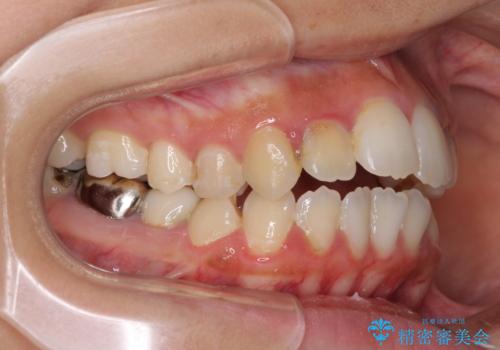

開咬と前突を改善 ワイヤー装置での抜歯矯正

- 口元の突出感と開咬を気にして来院された患者様です。

口元の突出感を改善するため、第一小臼歯を抜歯して口元を引っ込めることとしました。

一般的には上下左右の第一小臼歯4本を抜歯しますが、下顎に対して上顎が前方に位置しているため、まずは上顎小臼歯2本を抜歯し、治療経過を見て下顎小臼歯を抜歯するかどうかを決めていくこととしました。

元々むし歯の処置歯が多く、神経を取り除いている歯が多くありましたが、どうやら右上の前歯と小臼歯は外傷により神経を失った可能性があり、抜歯したスペース前後の歯が全く動かない状態でした。

結果として下顎の小臼歯は抜歯せず、右上の抜歯スペースはむし歯処置を兼ねてオールセラミックブリッジにて補綴治療を行うこととしました。